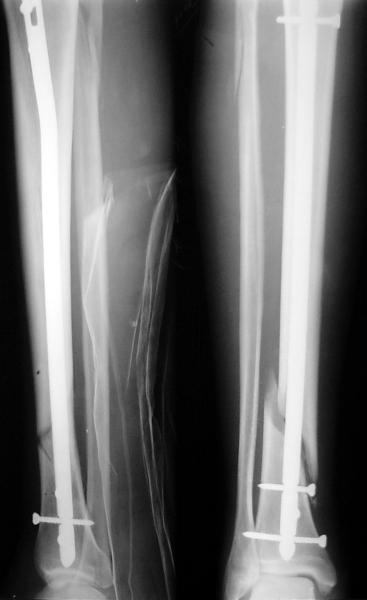

На мой взгляд, на снимках, приведённых Вами - неправильно сростающийся перелом дистальной трети большеберцовой кости, состояние после остеосинтеза интрамедуллярным гвоздём.

Как Вы пишите снимок под номером 1 - менсяц после операции, под номером 2- два месяца после операции.

Вы не послали послеоперационный снимок, поэтому трудно судить о состоянии редукции после операции.

Установка с медиальной стороны гвоздя в области дистального фрагмента дополнительного шурупа помогло бы Вам репонировать и удержать перелом в анатомическом положении, предотвратило варусную деформацию и смещение по ширине.

I think that the X-Rays show S/P IMN of Spiral # of the Distal Tibia consoles in misalignment.

You wrote that a picture number 1 - f month after the surgery, and number 2-two months after the surgery.

You have not sent a postoperative X-Rays; so it's impossible to discuss about the condition of a reduction after operation.

Let to express concerning technique of operation my opinion... Insertion of a screw to medial side of a nail in distal fragment would help you to reduction and to keep this fracture in anatomic position has prevented varus deformity and displacement on width. By the way, if it is possible send a postoperative picture.

Ok. А также и следующий, в 3 месяца.